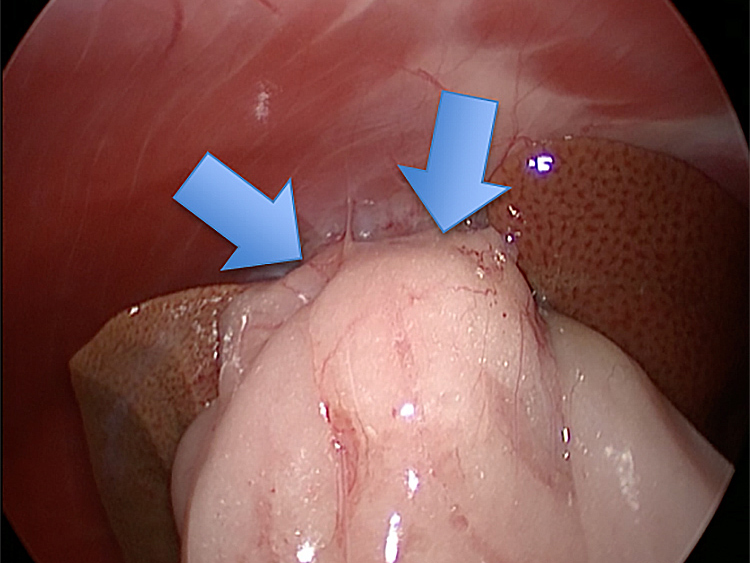

癒着(矢印)がひどく胆嚢を確認することができませんでした。 このように癒着しているときはギリギリで剥がすとひどく出血をおこすことがあるので無理にはがそうとしないで、脂肪の血管に注意しながら脂肪ごと剥がしていきます。

胆嚢(矢印)の取り囲むように肝臓や腸が癒着していました。肝臓の表面はボコボコしています。